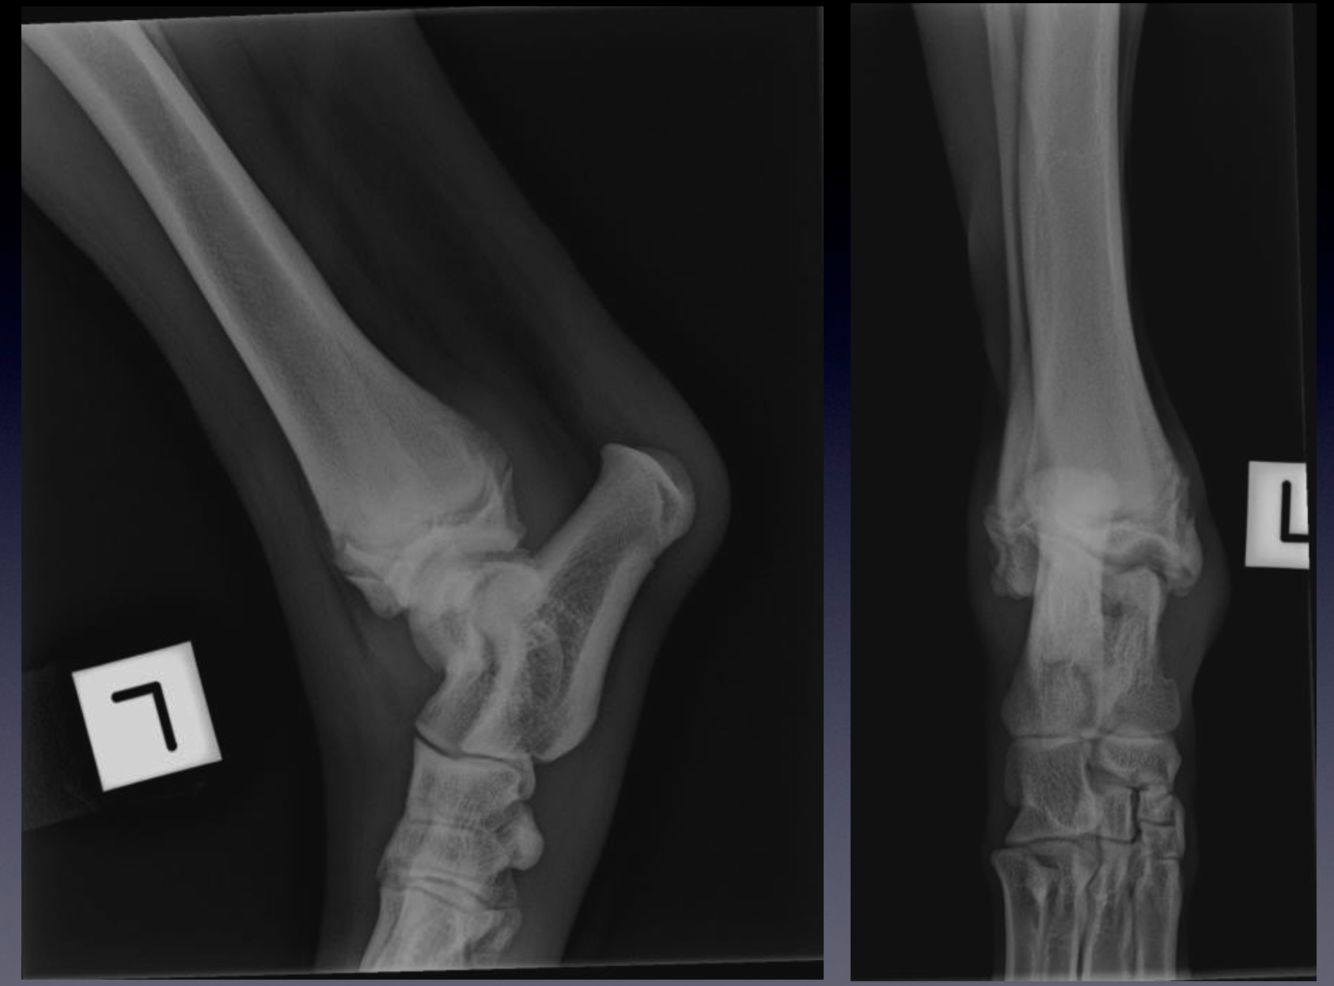

Case 1: Patient 239711

VIEW?

Compare these radiographs to the example of a normal tarsus.

Please note:

•

mild soft tissue swelling associated with the tarsocrural joint, best identified on the plantar aspect of the joint as

seen on the mediolateral view

widening of the medial aspect of the tarsocrural joint space

flattening of the medial trochlear ridge of the talus - you can see this on both dorsoplantar and mediolateral views

the small mineralised fragment present in the joint space proximal to the medial trochlear ridge of the talus, as

seen on the dorsoplantar view.

This is a case of osteochondritis dissecans (OCD) of the medial trochlear ridge of the talus. What are other

predilection sites for osteochondrosis in the dog?

Mediolateral and dorsoplantar projections of the tarsus of a skeletally immature dog.